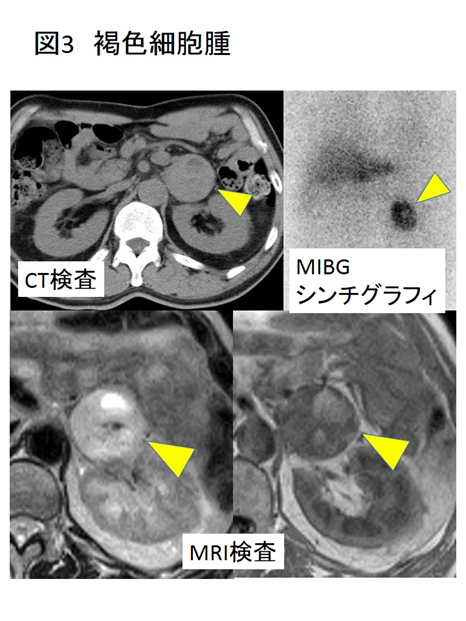

褐色細胞腫:カテコラミンを産生する腫瘍

MRIでどんな所見?(2017年)

てT1 強調像で低信号,T2 強調像で高信号→MIBGシンチで機能的診断できる